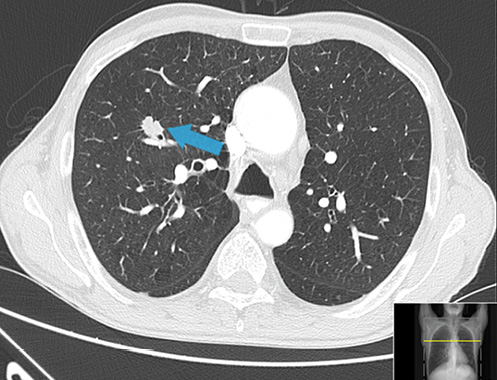

Strongyloidiasis is an infection caused by the helminth Strongyloides stercoralis, an intestinal nematode which is endemic in rural areas of tropical and subtropical regions of the world, particularly in hot and humid climates as well as countries with inadequate sanitary conditions, but it can also be transmitted in temperate regions such as North America and Southern Europe [1, 2] (Fig. 1).

Fig. 1: Map showing reports of the global prevalence of Strongyloides stercoralis infection in 2014 [1].

The global prevalence of strongyloidiasis is unknown, but experts estimate that there are between 30 and 100 million infected persons worldwide [3]. In Portugal there are no recent epidemiological data, but between 1914 and 1985 autochthonous cases of S. stercoralis infection were reported, suggesting endemic zones within the country in the past [4-6].

Distribution of S. stercoralis closely coincides with the geographic distributions of soil regimes, moisture, and temperature. The filariform larvae can survive with significant motility in water, greatly increasing their transmission potential. The most frequent mode of transmission is via skin contact with contaminated soil and poor water quality, which explains how the lack of adequate sanitation has a major influence, making strongyloidiasis a public health issue in these regions. Less common modes of transmission include fecal-oral transmission and person-to-person transmission via contact with fecally contaminated fomites.